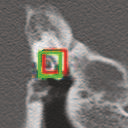

Deep learning based medical image segmentation models usually require large datasets with high-quality dense segmentations to train, which are very time-consuming and expensive to prepare. One way to tackle this challenge is by using the mixed-supervised learning framework, in which only a part of data is densely annotated with segmentation label and the rest is weakly labeled with bounding boxes. The model is trained jointly in a multi-task learning setting. In this paper, we propose Mixed-Supervised Dual-Network (MSDN), a novel architecture which consists of two separate networks for the detection and segmentation tasks respectively, and a series of connection modules between the layers of the two networks. These connection modules are used to transfer useful information from the auxiliary detection task to help the segmentation task. We propose to use a recent technique called "Squeeze and Excitation" in the connection module to boost the transfer. We conduct experiments on two medical image segmentation datasets. The proposed MSDN model outperforms multiple baselines.